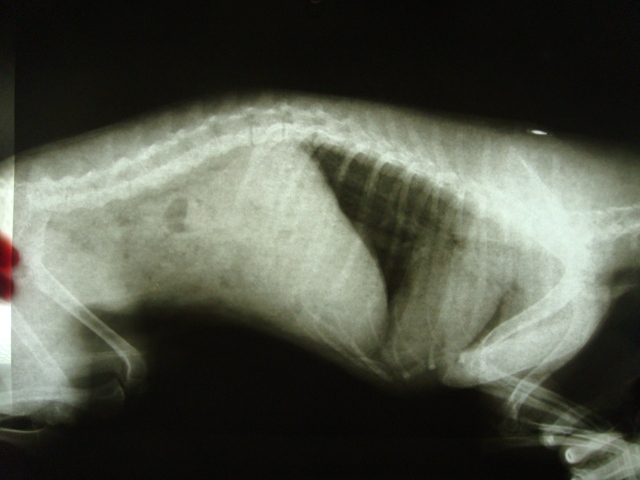

Кормила собаку комбинированно.Вроде не давала ничего жирного(все как надо было),только специально приготовленная пища,а на ужин корм!!!!В общем спустя месяц рич начал чахнуть,а ночью кричать от боли.Я схватила его в охапку и повезла к врачу.Сказали застряло инородное тело.Вливали масло вазелиновое.Сходил по большому,на следующий день он продолжил плакать.Я снова его повезла к врачу.Сделали узи:сосуды забиты желчью,увеличена печень.желудок в плохом состоянии